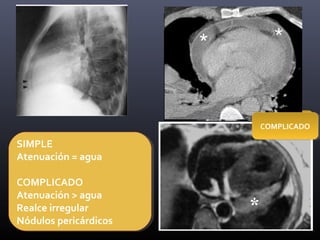

SIMPLE

Atenuación = agua

COMPLICADO

Atenuación > agua

Realce irregular

Nódulos pericárdicos